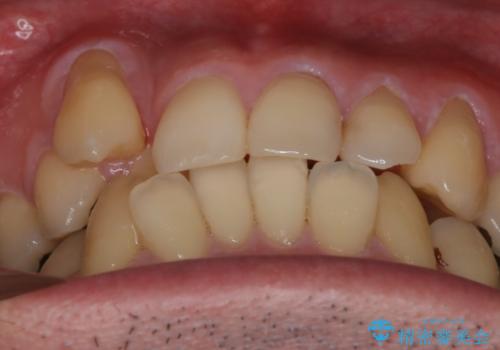

【メタル装置】1本のみ抜歯してワイヤー矯正

- 30代男性

抜歯の本数を最小限に抑えたことで、治療計画も1年5ヶ月と短期間で終了することができ

主訴である前歯のがたつきも改善され綺麗な歯並びになりました。

矯正の装置を除去したタイミングで、ホワイトニングも行うことで歯の色味も白くなりました。